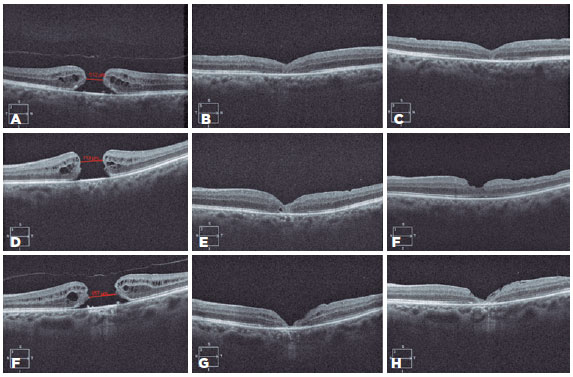

Anatomical surgical success was defined as MH closure on days 15 and 60 confirmed by 5-line raster B-scan OCT (horizontal and vertical scans) in each visit. During the analysis, the tomographic contour of the MH closure was evaluated and described as V-type (steep foveal contour), U-type (similar to the normal foveal contour), or flat open (foveal defect with a flattened cuff of retinal edema around borders). The recovery of the ellipzoid zone (EZ) and external limiting membrane (ELM) was also evaluated on 5-line raster B-scan OCT at the same levels during follow-up visits (horizontal and vertical central scans) through the observation of EZ and ELM defects. The evaluated layers were described as intact (complete layer restoration) or not intact (layer defect). The collected ETDRS visual acuity was converted to LogMAR. Visual success was regarded as a minimum progress of 0.3 LogMAR units (i.e., upgrade of 15 ETDRS letters).

The anatomical success rate was 95% (19/20). MHs with preoperative MLD <650 μm (12/20) achieved 100% closure, whereas those with MLD <650 μm (8/20) achieved 87.5% closure. Two closure types of MHs, namely, U- and V-type closure, were observed in 10 (52.63%) and 9 (47.36%) eyes, respectively. No statistical significance was found in the relationship between the MH size and closure type (U=23.500; p=0.079). Regarding OCT findings among 19 eyes with closed holes, 9 (47.36%) presented with ellipsoid zone and ELM defects, and 10 (52.63%) presented only an ellipsoid zone defect. The EZ and ELM defects resolved from day 15 to day 60 of follow-up, without statistical significance (Z=-1.633; p=0.102). Complete recovery of the EZ and ELM defects was observed in 3 (15.78%) eyes 2 months after surgery. The eyes without anatomical success presented hole closure on day 15 postoperatively; however, after 2 months, the OCT revealed the total damage of the retinal layers.

04-fig02.jpg)